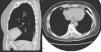

COMUNICACIONES CLÍNICAS

Dolor torácico agudo causado por necrosis de la grasa pericárdica: un diagnóstico a considerar en algunos pacientes

Acute chest pain caused by pericardial fat necrosis: a diagnosis to consider in some patients